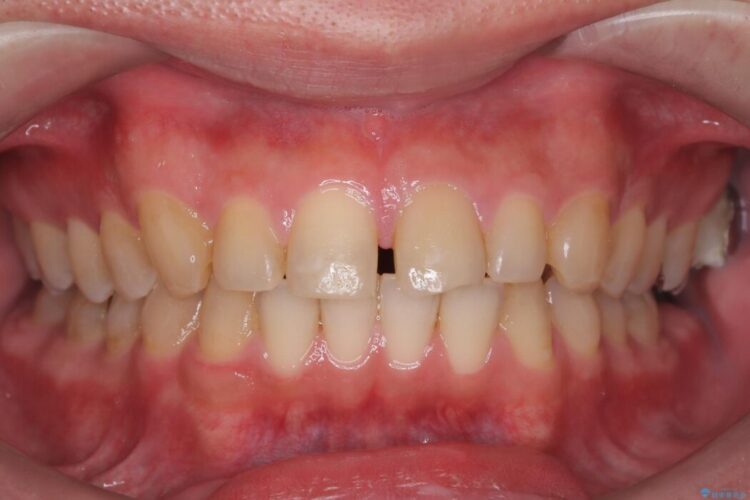

前歯の隙間とガタつきが気になるとご来院された患者様です。

正中離開・叢生のほかに、上下の奥歯が全く咬み合わないシザーズバイトの状態も認められました。